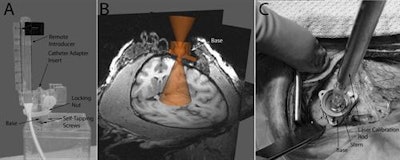

Images show technology and methodology involved in MRI-guided transplantation of neural stem cells into the Parkinsonian brain. Courtesy of Cell Transplantation.Lead author Dr. Marina Emborg, PhD, and colleagues developed an MRI-compatible trajectory guidance system that has been successful for intraoperative MRI. Most recently, they upgraded the system for real-time targeting and guidance, which allows for real-time pressure readings that can prevent clogging during cell delivery.